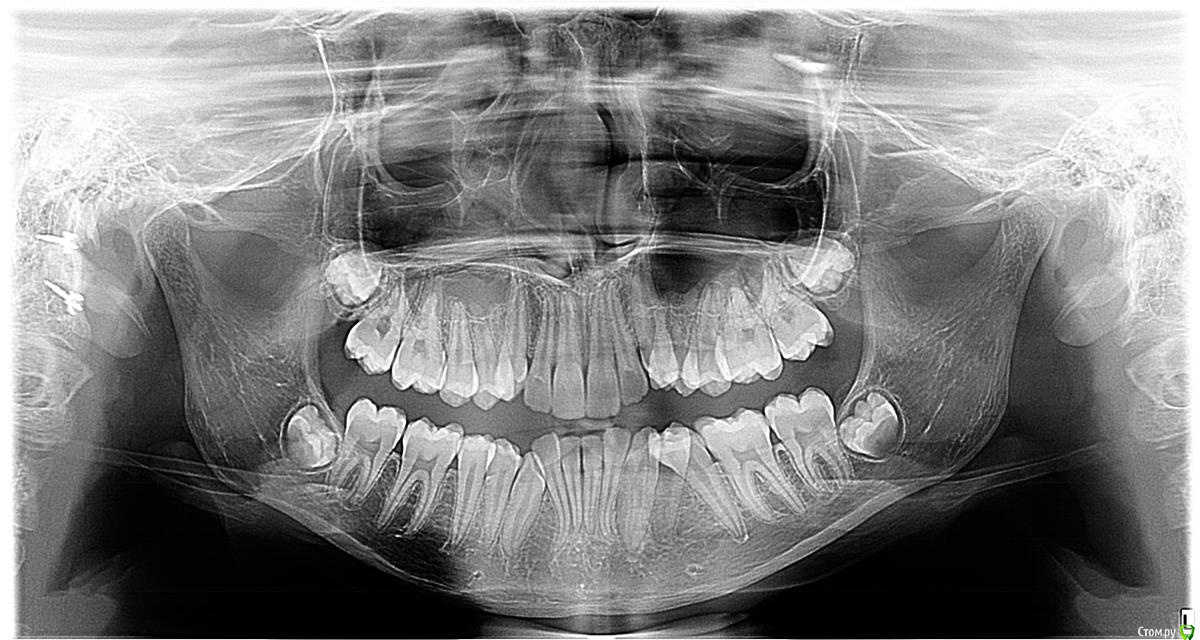

НОЛЬ Опубликовано 9 февраля, 2020 Поделиться Опубликовано 9 февраля, 2020 Прошу совета у специалистов!!! Мнения докторов у которых были на консультации неоднозначны. ВОПРОС: Возможно ли исправить ситуацию посредством скоб или брекетов.. или надо удалять..??? Возраст девочки 13 лет. Ссылка на комментарий